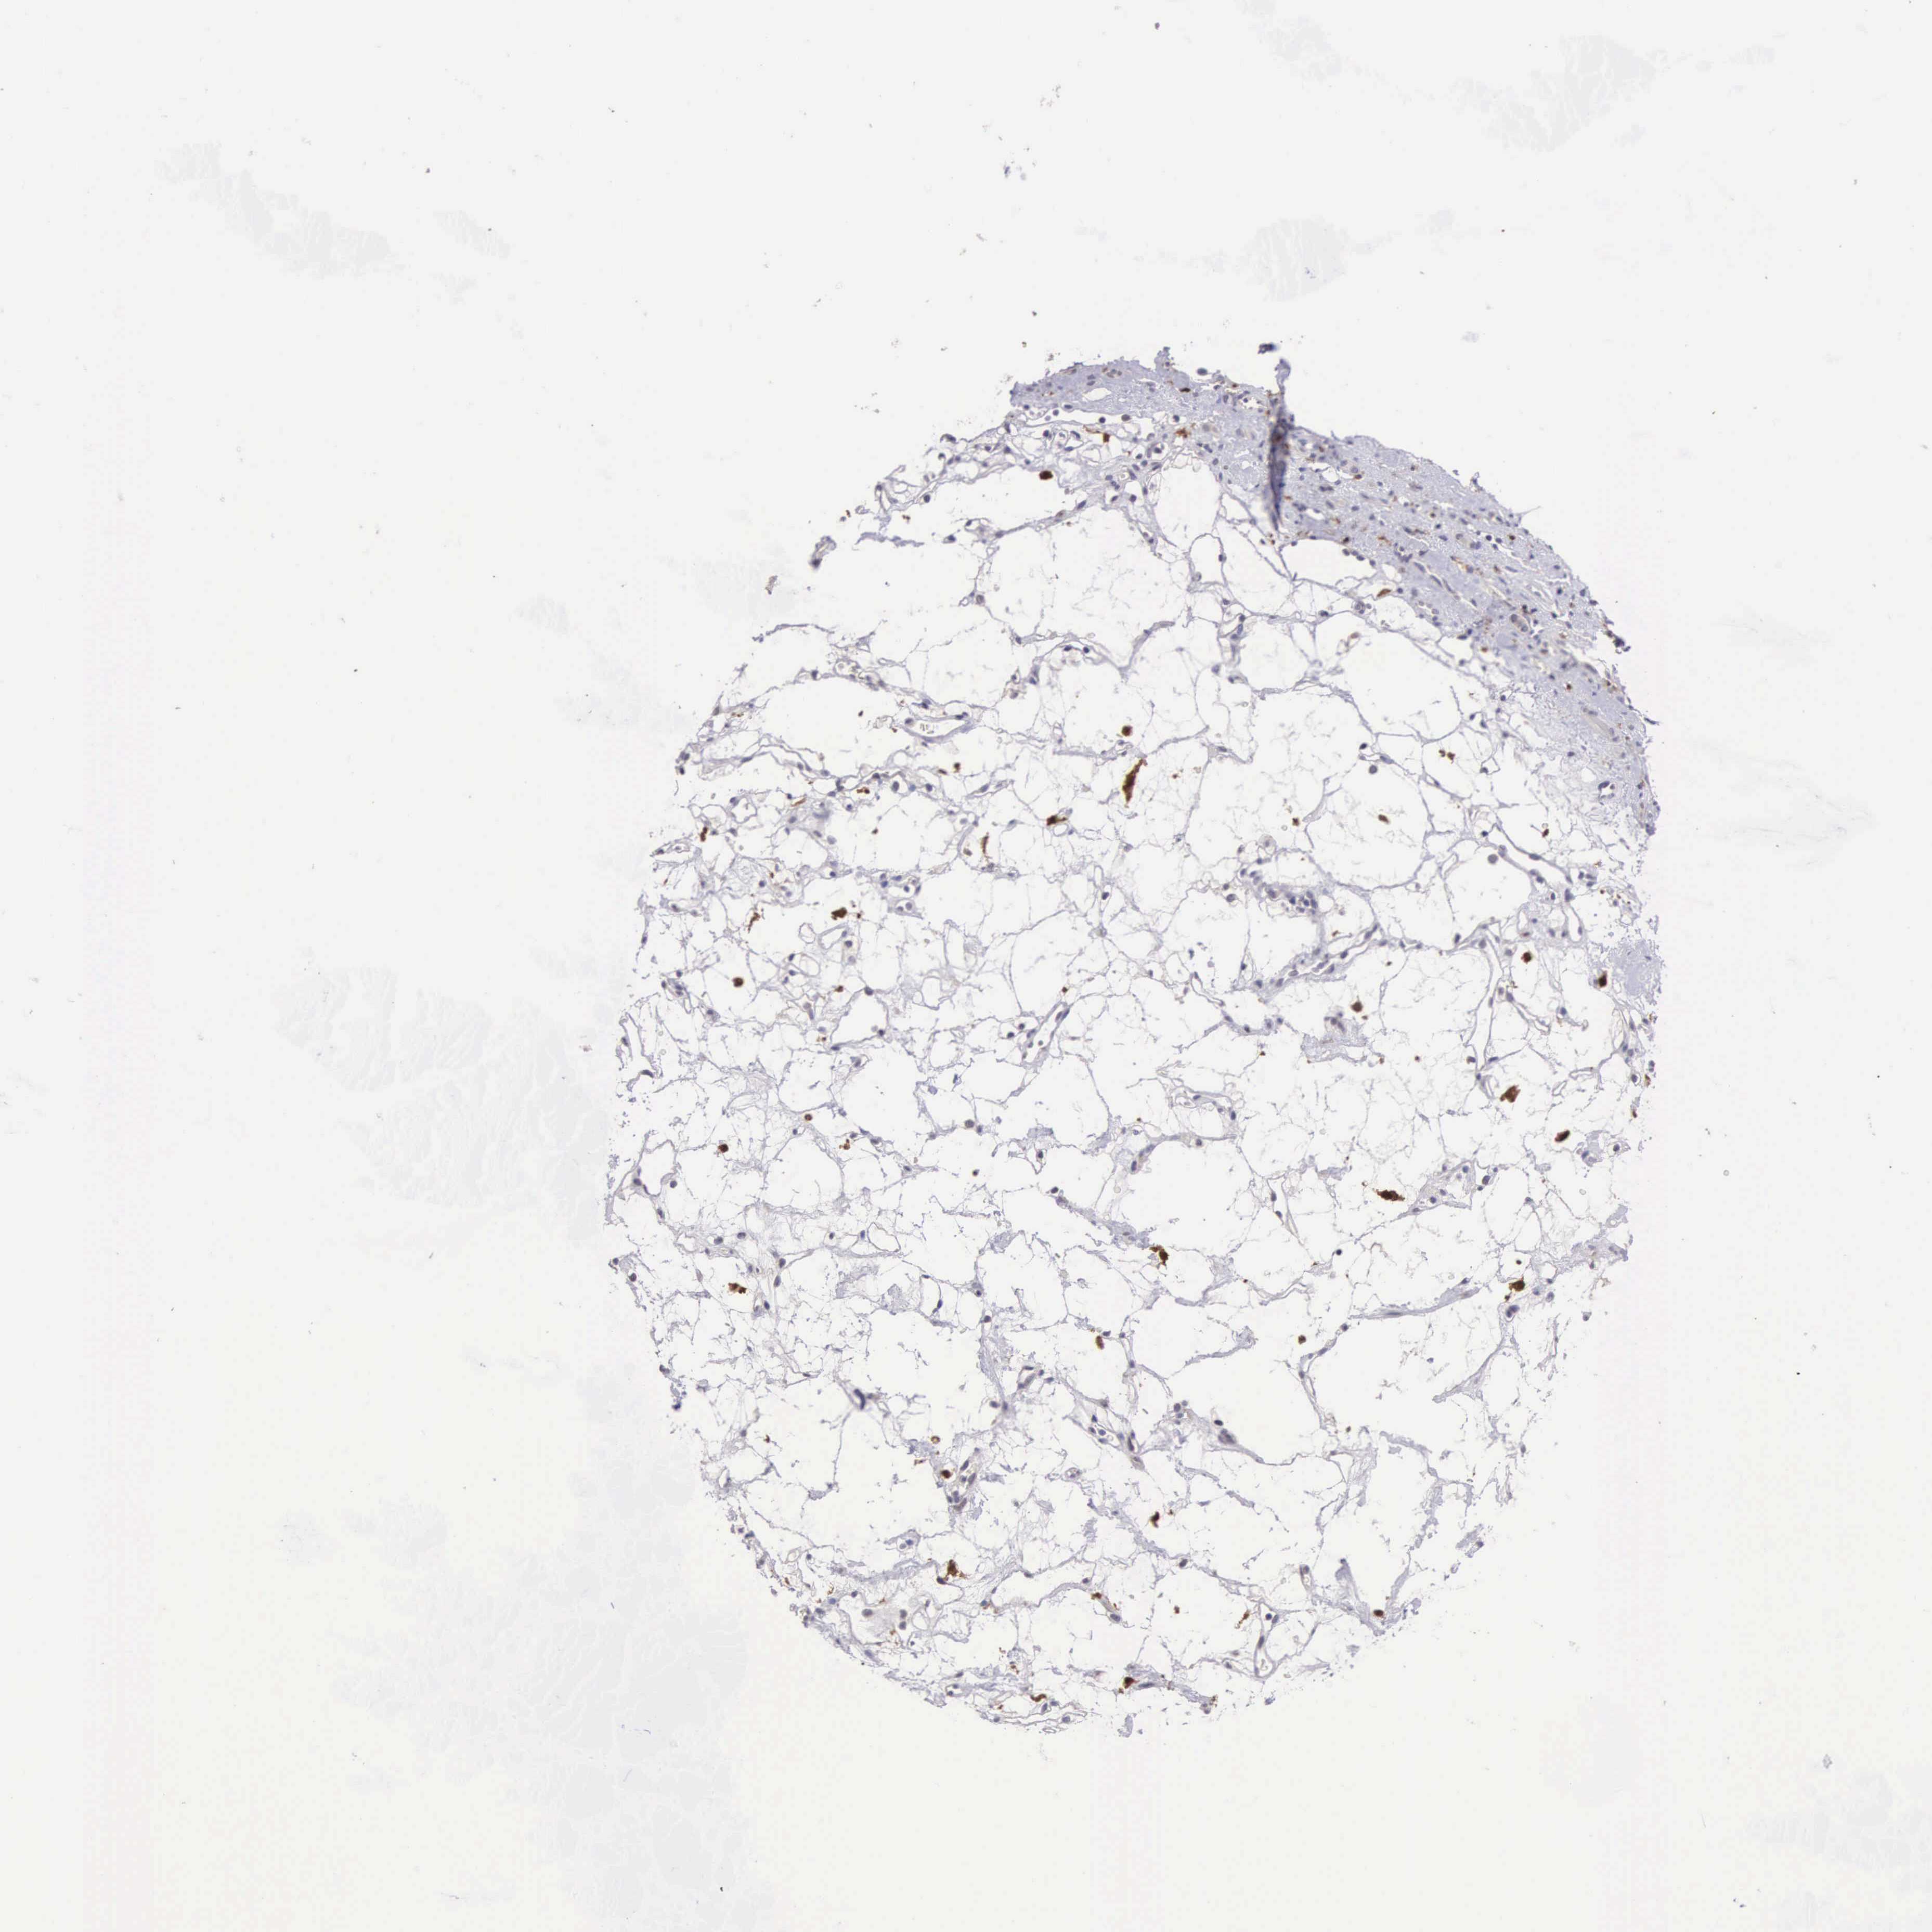

KIDNEY RENAL CLEAR CELL CARCINOMA (TCGA) - Interactive survival scatter ploti

The Survival Scatter plot shows the clinical status (i.e. dead or alive) for all individuals in the patient cohort, based on the same data that underlies the corresponding Kaplan-Meier plots. Patients that are alive at last time for follow-up are shown in blue and patients who have died during the study are shown in red.

The x-axis shows the expression levels (FPKM) of the investigated gene in the tumor tissue at the time of diagnosis. The y-axis shows the follow-up time after diagnosis (years). Both axes are complimented with kernel density curves demonstrating the data density over the axes. The top density plot shows the expression levels (FPKM) distribution among dead (red) and alive patients (blue). The right density plot shows the data density of the survived years of dead patients with high and low expression levels respectively, stratified using the cutoff indicated by the vertical dashed line through the Survival Scatter plot. This cutoff is automatically defined based on the FPKM cutoff that minimizes the p-score. The cutoff can be changed by dragging the vertical line or by entering a cutoff value in the square labeled "Current cut-off".

Under the Survival Scatter plot the p-score landscape (black curve; left axis) is shown together with dead median separation (red curve; right axis). Dead median separation is the difference in median mRNA expression between patients who have died with high and low expression, respectively. It is calculated as follows: median FPKM expression of dead patients with high expression - median FPKM expression of dead patients with low expression. This is intended to aid the user in visually exploring custom cutoffs and the associated p-scores and dead median separation.

Individual patient data is displayed and can be filtered by clicking on one or more of the category buttons on the top of the page. Categories describing expression level and patient information include: high, low, alive, dead, female, male and tumor stages. The scale of the x-axis can be toggled between linear and log-scale by clicking on the "x log" button. Mouse-over function shows TCGA ID, patient information and mRNA expression (FPKM) for each patient.

& Survival analysisi

Kaplan-Meier plots summarize results from analysis of correlation between mRNA expression level and patient survival. Patients were divided based on level of expression into one of the two groups "low" (under cut off) or "high" (over cut off). X-axis shows time for survival (years) and y-axis shows the probability of survival, where 1.0 corresponds to 100 percent.

CDC45 is validated prognostic, high expression is unfavorable in Kidney Renal Clear Cell Carcinoma (TCGA)

: 2.62

Average pTPM 2.0

Number of samples 521